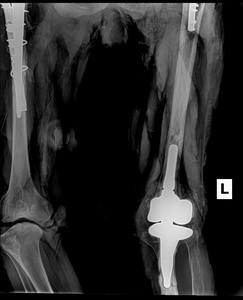

Numerous cadavers have been dissected throughout the years at our chiropractic institution to enable students to learn about normal and even abnormal anatomy to further their medical education. A cadaver of a 47-year-old Caucasian female with a cause of death of thrombocytopenia absent radius syndrome (TARS) sparked our interest in learning more about this syndrome and how chiropractic modalities may be of benefit in helping in daily activities in such patients. There were several interesting findings noted as the complete dissection of the cadaver was performed. We decided to get x-rays (after dissection) of the cadaver for documentation of the different abnormalities and surgical procedures. Radiographic findings noted in this cadaveric case demonstrate the absence of radii. In addition, post-mortem (post-dissection) radiographs showed a total right hip replacement, a total left knee replacement, and surgical repair with plate and screw placement of the left femur (See Figures 3a and 3b).3

These surgical repairs were most likely due to osteoarthritic changes in the bone related to the disease. To support the reasoning for the repairs being due to probable arthritic changes, there were gross findings of arthritic changes of the right knee and hypoplasia of the patella, a finding seen with TARS (See Figure 4).